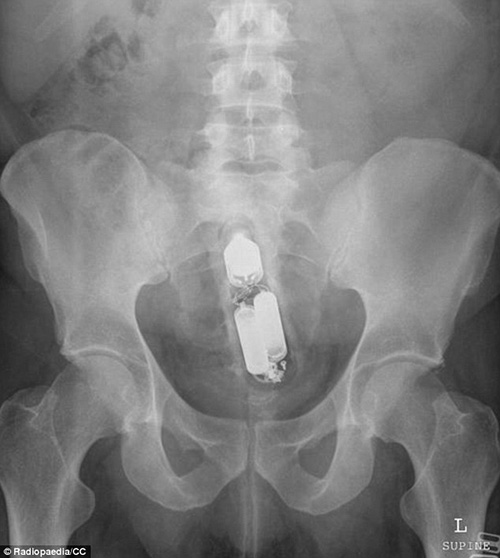

VBF- Đây là các hình ảnh được cung câp bởi các bã sĩ trong bệnh viện. Các bênh nhân sau khi để lọt các đồ vật vào người đã phải đi cấp cứu tại bệnh viện và đã được chụp X-quang để xác định đồ vật đó.Đó thường là những "vật dụng bất bình thường" được các bác sĩ khắp thế giới tìm thấy bên trong trực tràng của các bệnh nhân và chia sẻ trên trang Radiopaedia, một website giáo dục và thảo luận do các sinh viên X-quang thành lập từ năm 2005. Hình ảnh X-quang được chia sẻ trên website là vật mẫu cho việc nghiên cứu hợp tác và là giáo cụ trực quan trong giảng dạy ngành học quang quyến (môn học X-quang), hoặc dùng làm tài liệu cho các bảo tàng, đồng thời là những ví dụ giúp mọi người cảnh giác. hiếc chày trong trực tràng người đàn ông 40 tuổi được "khổ chủ" giải thích khi nấu món ăn Malaysia đã bị trượt vào trong??? Một chai đựng cà phê với những chiếc ghim gắm vào lớp cao su phía dưới nắp được bệnh nhân đưa vào trong cơ thể. Một tuýp đựng vitamin được đưa vào trong trực tràng. Thậm chí một chiếc chai cũng nằm trong danh sách bộ sưu tập các bác sĩ X-quang thu thập được. Dụng cụ rung được đưa vào qua đường hậu môn. tm tm